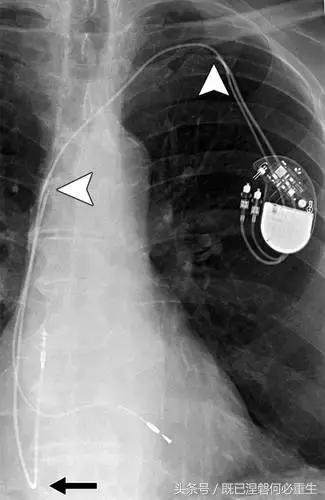

图。 6A 75岁的男性患有心房导线脱位。

A,Medtronic双腔起搏器的右心房导联(箭头)显示在正面(A)和外侧(B)图像上的纯垂直路线。 电极在心房中自由浮动。 患者抱怨经常心悸,并且设备检查显示不能可靠地去极化心房。 心房导线修订(未示出)导致心悸消除。 心房导线的推荐放置位于右心耳,但右心房中的导联可充分发挥作用。 在任一位置正确固定到壁上的引线通常将显示一定程度的曲率。

图。 6B 75岁的男性患有心房导线脱位。

B,Medtronic双腔起搏器的右心房导联(箭头)在正面(A)和侧面(B)图像上显示纯垂直路线。 铅在心房中自由浮动。 患者抱怨经常心悸,并且设备检查显示不能可靠地去极化心房。 心房导线修订(未示出)导致心悸消除。 心房导线的推荐放置位于右心耳,但右心房中的导联可充分发挥作用。 在任一位置正确固定到壁上的引线通常将显示一定程度的曲率。